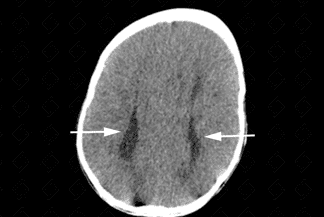

Descrição das imagens: Tomografia computadorizada do crânio. Imagem no plano axial mostra dilatação dos cornos occipitais dos ventrículos laterais (colpocefalia - seta vermelha). Além disso, é importante observar o paralelismo dos ventrículos laterais (setas brancas), algo habitualmente visto na disgenesia do corpo caloso.

Exames de imagem: Melhor pista diagnóstica é a ausência parcial ou completa do corpo caloso na linha média dos planos sagital ou coronal + ventrículos laterais separados e paralelos (axial), aparência de "cabeça de búfalo" ou "cabeça de alce".